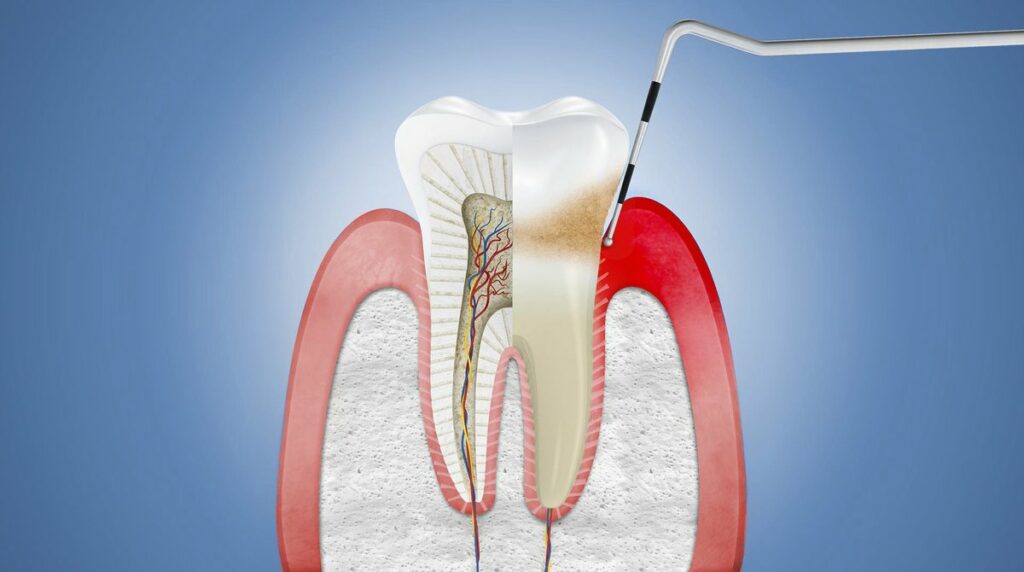

Что делать, если откололся кусок зуба: советы и рекомендации

Раздел: Необычные решения